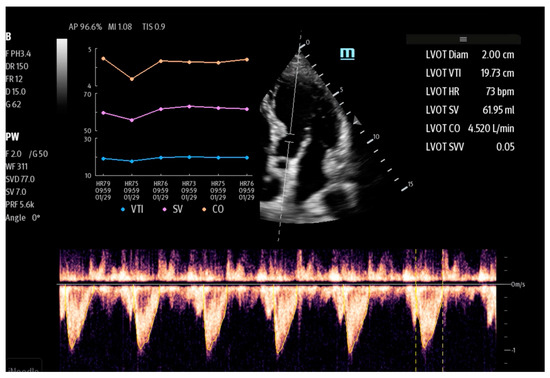

| Lvivo | Philips | automatic measurement of stroke volume (SV) and cardiac output (CO) | Ultrasonographic assessment of cardiac function |

| AutoVTI | GE | ||

| US2.AI | EchoNous | ||

| SmartVTI | Mindray | ||

- Zhai, S.; Wang, H.; Sun, L.; Zhang, B.; Huo, F.; Qiu, S.; Wu, X.; Ma, J.; Wu, Y.; Duan, J. Artificial intelligence (AI) versus expert: A comparison of left ventricular outflow tract velocity time integral (LVOT-VTI) assessment between ICU doctors and an AI tool. J. Appl. Clin. Med. Phys. 2022, 23, e13724. [Google Scholar] [CrossRef]

- Shaikh, F.; Kenny, J.E.; Awan, O.; Markovic, D.; Friedman, O.; He, T.; Singh, S.; Yan, P.; Qadir, N.; Barjaktarevic, I. Measuring the accuracy of cardiac output using POCUS: The introduction of artificial intelligence into routine care. Ultrasound J. 2022, 14, 47. [Google Scholar] [CrossRef]

- Shiran, C.; Barjaktarevic, I. VenueTM Family, Auto Tool for Measuring VTI. GE Healthcare, White Paper 2021. Available online: https://www.pocushub.net/data/venue-family_auto-vti_whitepaper_pocus__glob_jb02194xx.pdf (accessed on 1 January 2024).